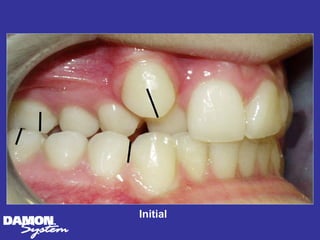

Initial 16 yearsโ€“ 5 months Class II, severe crowding, bilateral posterior crossbite